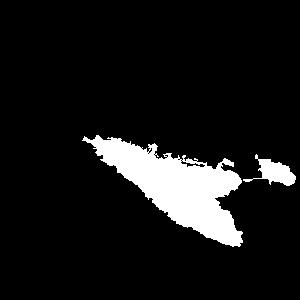

Figure 2a. illustrates the information retrieved from this CNN model from various layers of the architecture that is used to create a BAM map, which is used to segment the burn injury from normal skin in a 2D image. First, the heatmaps for the activations of the first convolutional layer are computed (Figure 2a(ii)), and then Grad-CAM heatmap is computed using the last convolutional layer (Figure 2a(iii)). Once the first convolutional layer heatmaps and Grad-CAM are generated, the algorithm uses a three-round iterative process to select activation heatmaps that have the highest correlation to the Grad-CAM heatmap among the channels of the first layer activations. After the process of correlating and selecting heatmaps is completed (Figure 3 ), segmentation masks are created next (Figure 4). A final composite BAM mask is created as illustrated in 2b(i). Finally, figure 2b (ii-iii) illustrates how the BAM mask is superimposed on the input image to segment the burn injury area, and how edge detection may be applied to the BAM mask in order to obtain a fine-tuned segmented boundary superimposed on the input image.

Figure 5 shows several burn image examples of patients with different sized burns in different body locations, for which the Grad-CAM heatmap, BAM heatmap, BAM masks, and final superimposed images were created. These results allow us to understand the clinical accuracy of burn segmentation from 2D images using BAM. These images show various degrees of burn. It is evident from the results that given skin burn images and the corresponding Grad-CAM heatmaps highlighting the burn regions even partially, the BAM heatmap is able to highlight the burn regions and display a high resolution heatmap accurately. This is the main contribution of BAM. It can be seen from the figure that the BAM heatmaps display different contrast levels in highlighting the burn regions. More precisely, the more superficial burns are highlighted with a lower contrast to the normal skin. The deeper burns, on the other hand, are highlighted with a higher contrast to the normal skin. Nevertheless, the contrast between the burn regions and the normal skin in the BAM heatmaps is sufficient for generating the binary segmentation masks even for the more superficial burns. As evidenced, the BAM heatmaps can successfully be converted into accurate binary segmentation masks. The rightmost column of the figure shows the BAM segmentation masks on top of the input images in order to better visualize the effectiveness of BAM in segmenting the burn regions. In short, comparing the Grad-CAM heatmaps against the BAM heatmaps and BAM segmentation masks provides evidence for a significant improvement in generating heatmaps that are both class-discriminative and fine-grained.